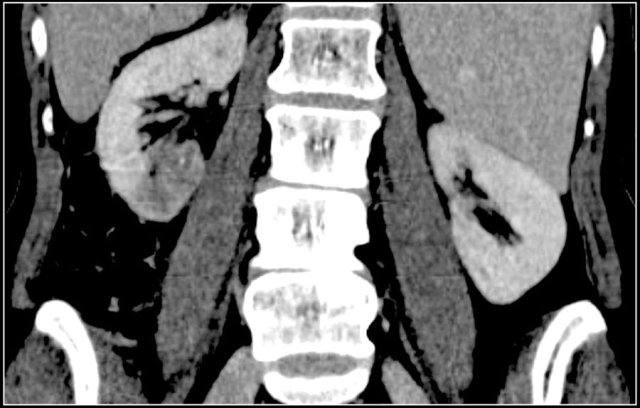

Renal abscess is usually a complication of acute pyelonephritis and patients present with urinary tract infection, flank pain and fever.

On CT a renal abscess usually presents as a non-specific homogeneous low attenuation lesion or as a complex cystic lesion.

The renal abscess may have a thick irregular enhancing wall with infiltration of the perirenal fat (figure).

In patients with an atypical clinical presentation the complex cystic appearance and extension into the perirenal fat may simulate a renal cell carcinoma.

This patient had a typical presentation with right flank pain and laboratory findings consistent with a urinary tract infection.

The ultrasound image shows a hypoechogenic lesion with some echolucency, which indicates a fluid-containing component.

This proved to be an abscess.